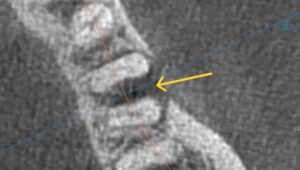

【近心根と分岐部に透過像がある】

【黄色矢印が透過像】

【CT画像 頬側と分岐部に骨がない】

【黄色矢印 骨消失部分】